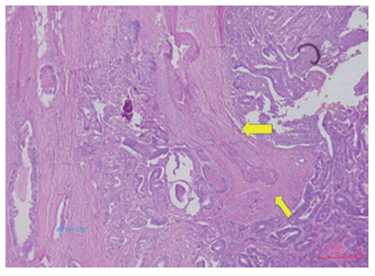

Figura 7. Infiltración perineural. Hematoxilina y eosina, 100X.